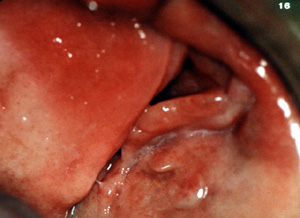

Aquí son dos épulis, bilaterales, en los vestíbulos del maxilar. Es una apariencia típica. Son lobulados  y muestran áreas focales aumentadas de vascularidad. En la porción central de cada masa hay una ranura ó una invaginación  que corre en una dirección anterior-posterior. La pestaña de la dentadura postiza encajará en estas ranuras.

Esta vista más aumentada de la lesión del lado izquierdo  está compuesta de por lo menos tres pliegues de tejido bastante denso. Hay invaginaciones profundas entre los pliegues.

Aquí la dentadura postiza está en el lugar y usted notará como el borde o pestaña de la dentadura se introduce en la invaginaciones. Esto indicaría que hay espacio considerable entre la pestaña y  reborde alveolar. La irritación constante por el borde de la dentadura postiza que choca con en el tejido mucoso da lugar a la producción continua de tejido conjuntivo fibroso inflamado.